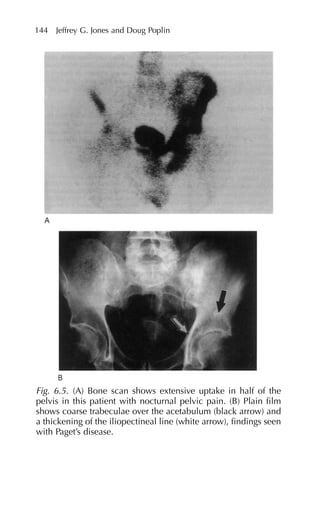

Fig. 1.1. Radiologic studies of the lumbar spine. (A) Plain radi-

ograph demonstrating a compression fracture of the L2 vertebral

body due to multiple myeloma. (B) CT scan demonstrating

nucleus pulposus herniating posteriorly into the spinal canal. (C)

MRI demonstrating an enhancing intramedullary metastatic

lesion in the cauda equina at the L1 level.